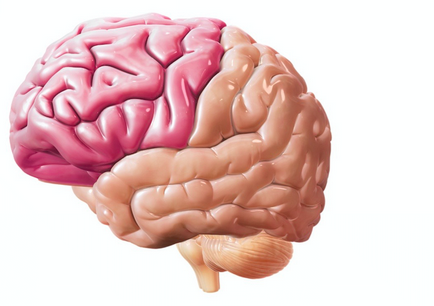

In creierul uman, oamenii de știință au identificat trei părți principale: cerebel, mezencefal și părții frontale a creierului. Toate trei sunt bine sa uitat deja la un embrion de patru săptămâni, ca „vezicule creier.“ Punct de vedere istoric mai vechi sunt considerate a fi partea din spate și mezencefal. Ele sunt responsabile pentru funcțiile interne vitale ale organismului: mentinerea fluxului sanguin, respirație. Pentru forma umana de comunicare cu lumea exterioară (gândire, memorie, de vorbire), care va fi de interes pentru noi în primul rând în lumina problemelor discutate în această carte, se întâlnește forebrain.

- Primul principiu este acela de a separa funcțiile emisferelor - lateralization. Creierul este împărțit fizic în două emisfere: stânga și dreapta. In ciuda asemanarii fizice și interacțiune activă, oferă un număr mare de fibre speciale, asimetria funcțională a creierului pot fi urmărite destul de clar. Cu unele funcții mai bune la emisfera dreapta (în majoritatea oamenilor, este responsabil pentru activitatea de creație și figurativ). iar celălalt stânga (asociat cu gândirea abstractă, activități simbolice și raționalitate).

- Al doilea principiu este de asemenea asociat cu distribuirea funcțiilor în diferite zone ale creierului. Cu toate că acest organism funcționează ca un întreg și multe dintre funcțiile umane superioare sunt furnizate de operațiune coordonată a diferitelor părți ale „diviziunea muncii“ între lobii cortexul cerebral pot fi urmărite destul de clar.

In cortexul poate distinge patru lobi: occipitale, parietale, temporale și frontală. Conform unui prim principiu - lateralization - fiecare pereche are partea sa.